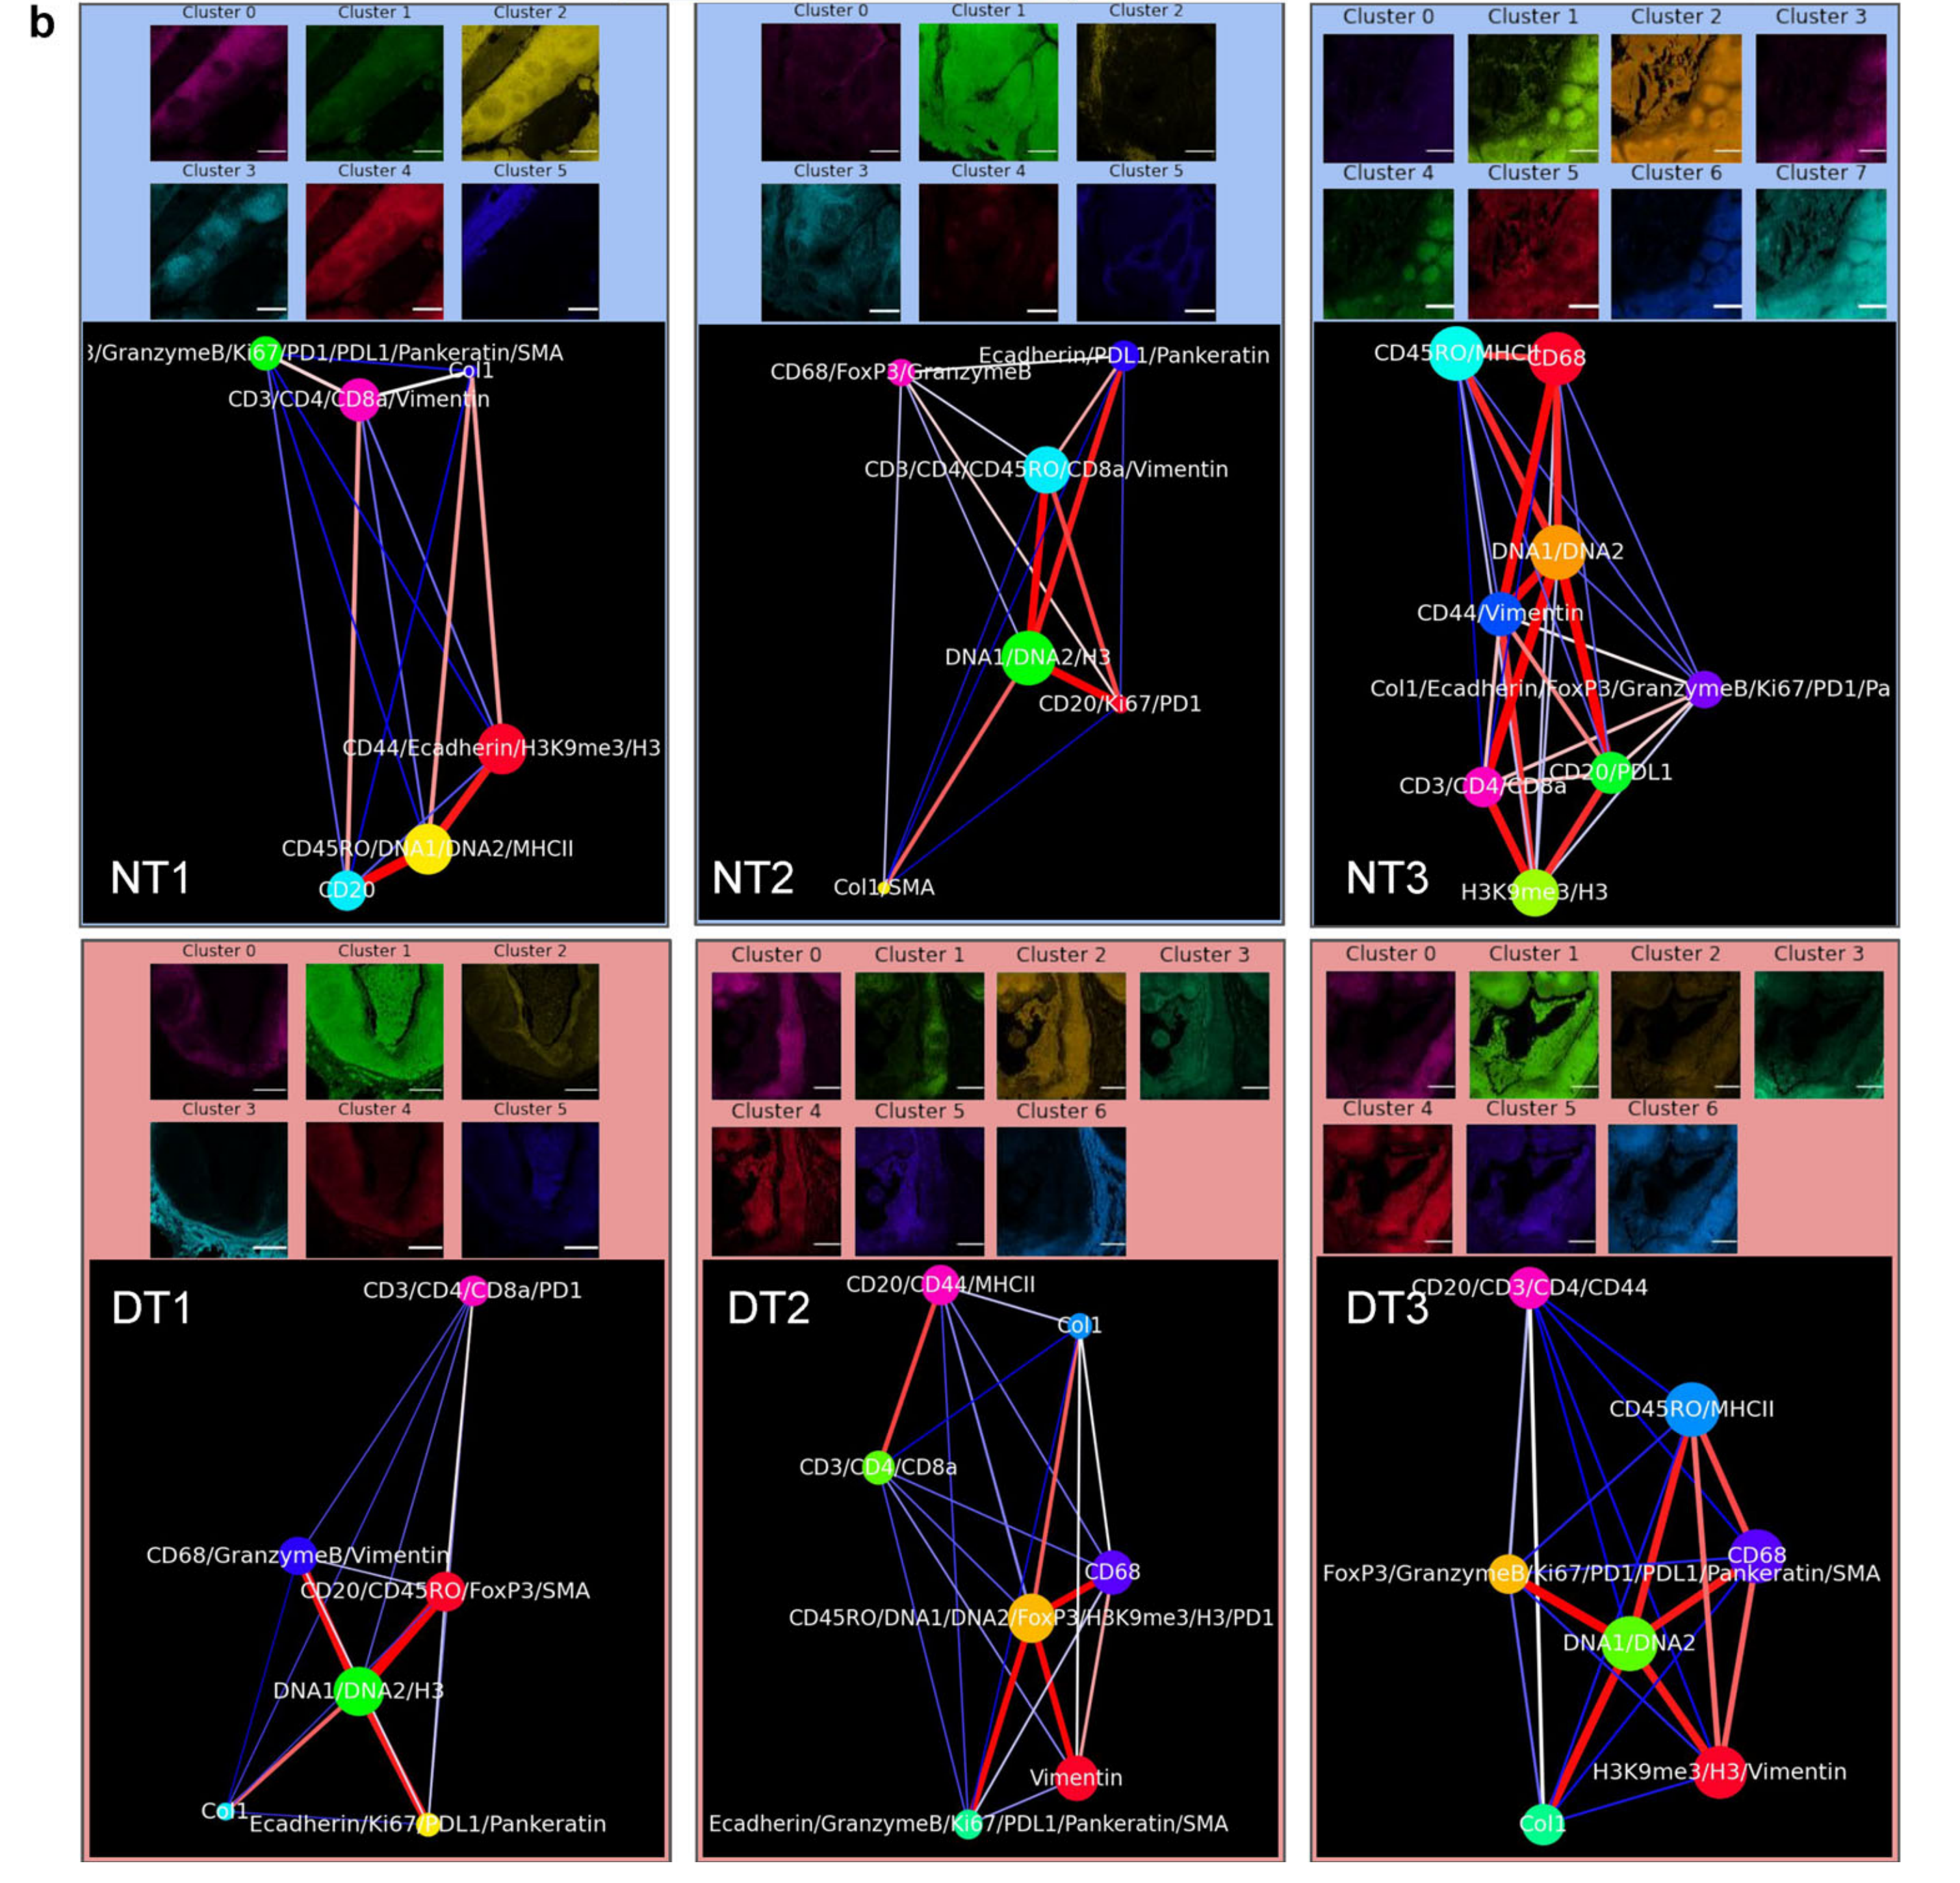

What is the spatial localization and expression correlation between markers in both healthy and diseased tissues?